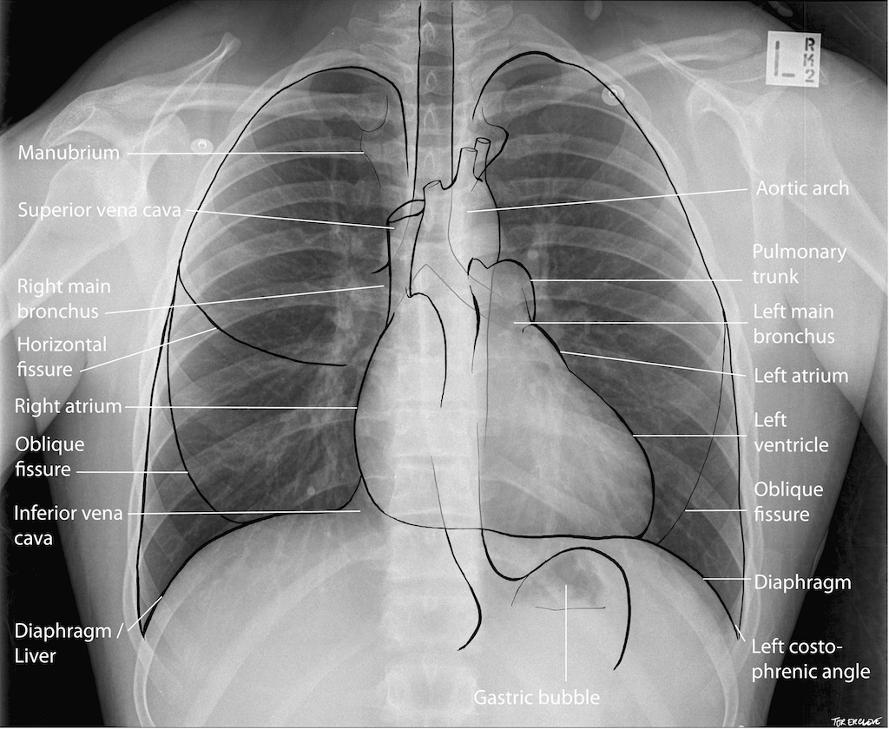

건강 검진이라면 빠지지 않는 흉부 엑스레이다.

다시 흉부 엑스레이 사진이다.

이 한 장의 필름에 무수히 많은 정보가 있다.

이 사진이 '정상'이라는 판독이 나오기까지,

의사가 '정상'이라고 자신 있게 말하기까지,

모든 질환의 가능성을 열어두고 고민하는 '겸손함'은 매우 중요하고, 이것은 많은 시간과 노력을 투자한 교육과 수련을 통해서만 가능하다.

아무리 많은 사진을 접한 영상의학과 전문의도 판독자 '아무개'라는 이름이 찍히는 무게감과 부담감을 느끼지 않을 수 없다.